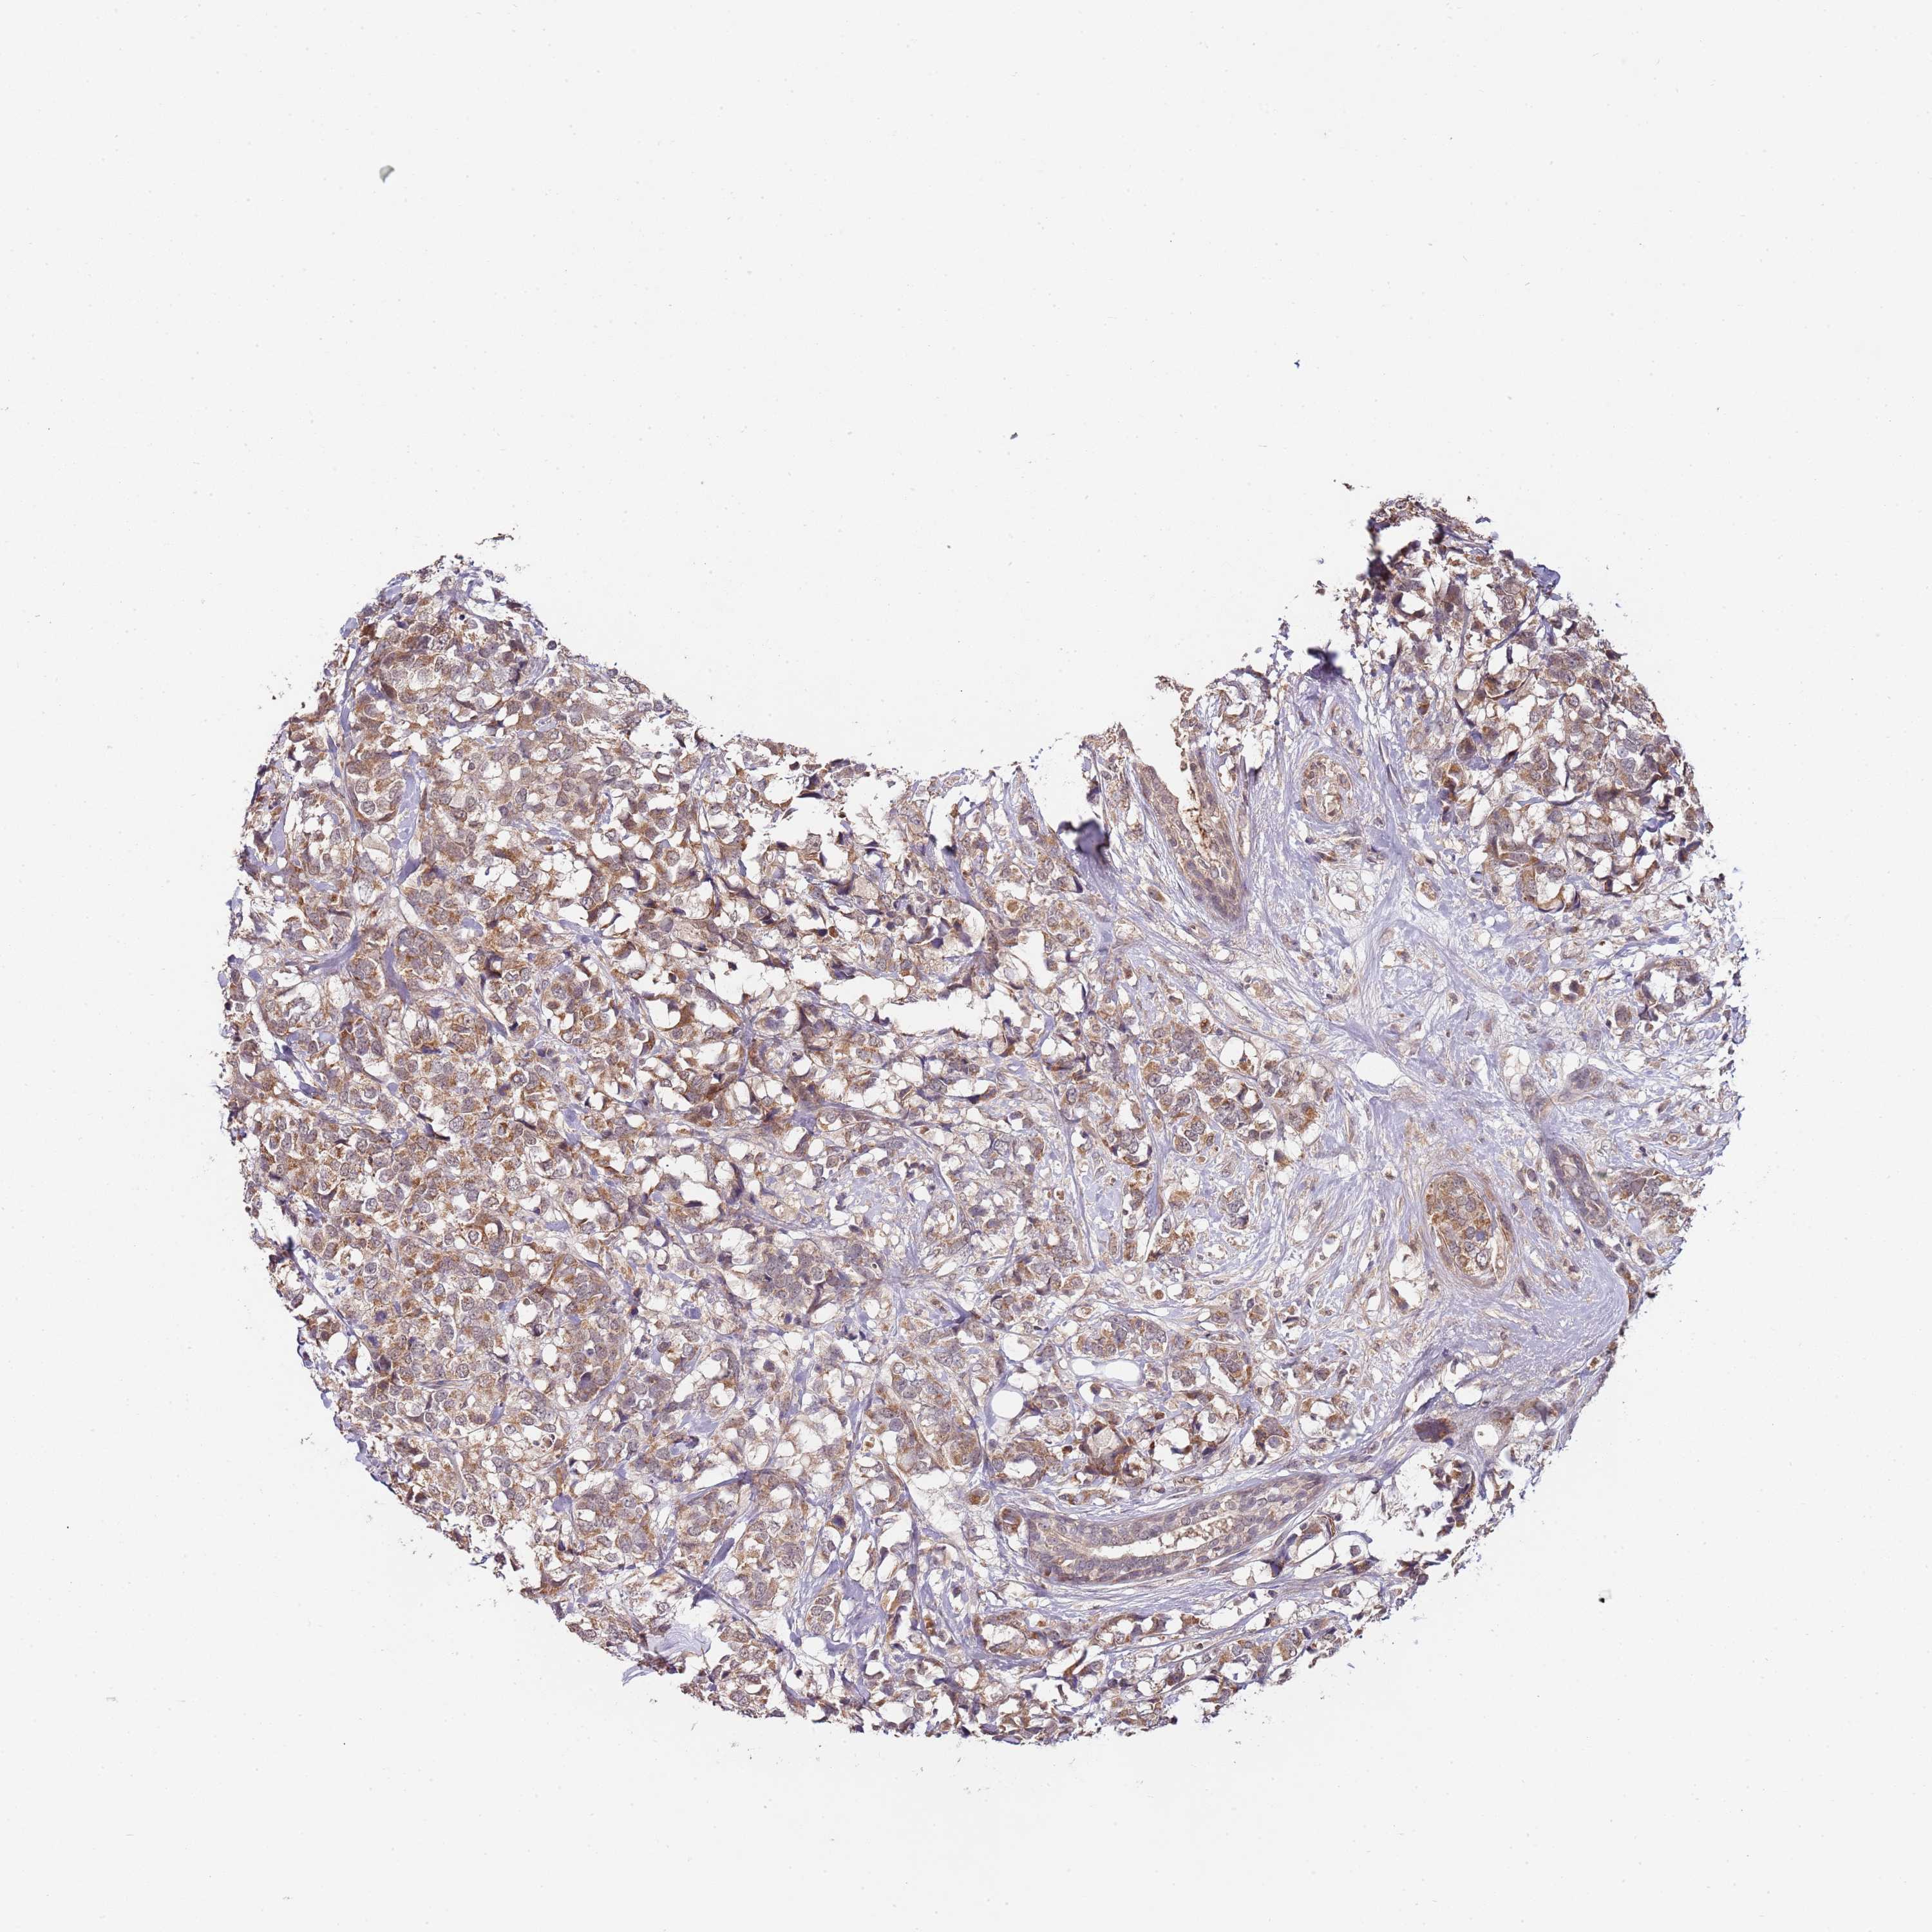

BRCA TCGA BRCA VALIDATION PROTEIN EXPRESSION